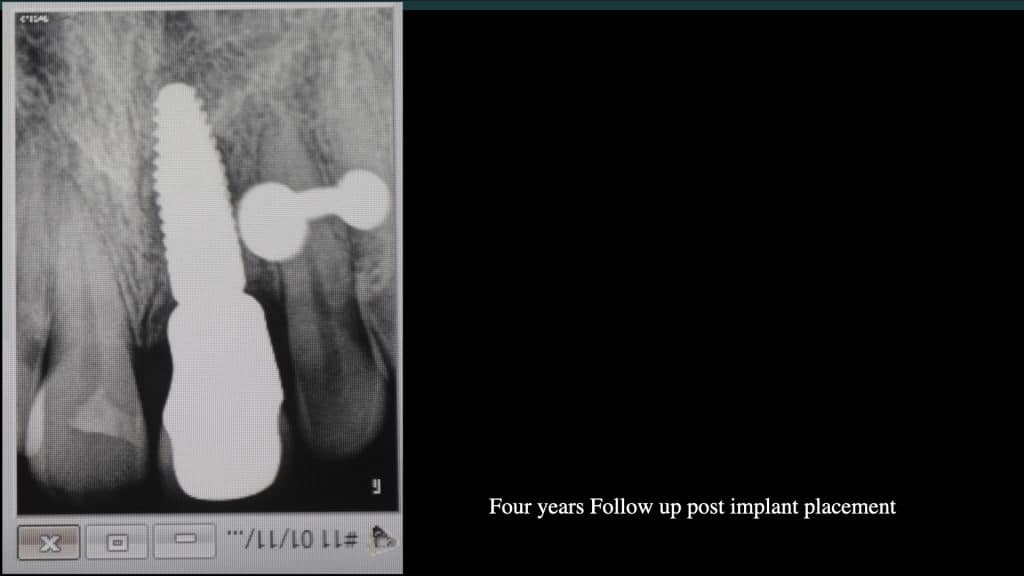

A 27-year female patient with dislodged Resin bonded FPD. She had that FPD for past few years, it had metal wings on palatal surfaces of UR1 and UL2 and a post like metal extension into the root canal of UL1. There was gingival abscess due to fractured root segment most probably due to extended metallic post like structure. Immediate implant placement (IIP) and Immediate restoration (IR) was planned for this patient.

Immediate post-op